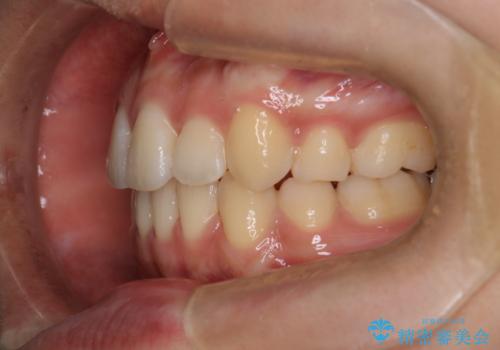

- 八重歯を主訴に来院されました。4番の歯を4本抜歯し、八重歯を並べる計画をたてました。

抜歯をし、スペースを確保したことにより八重歯をきれいに並べることが出来ました。